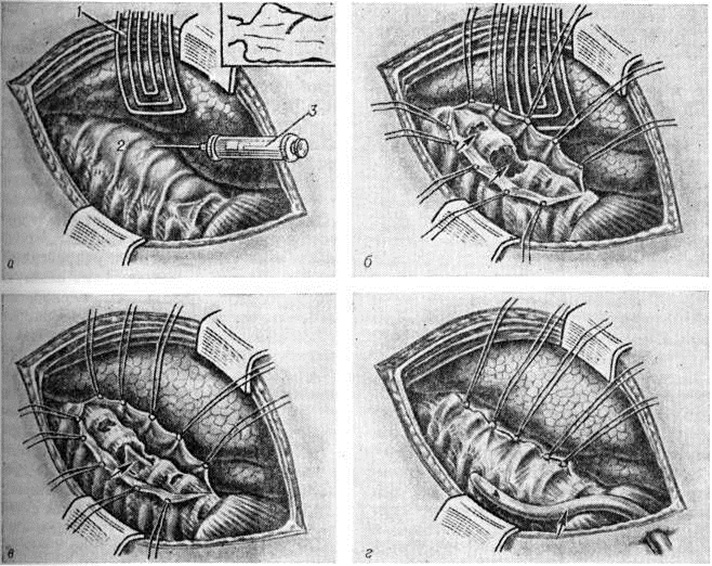

Операции при Спондилит условно делят на несколько основных групп (радикальные, стабилизирующие, радикально-восстановительные, декомпрессионные, паллиативные и другие). Радикальными операциями являются некрэктомия тел позвонков (смотри полный свод знаний: Некрэктомия) или их резекция. Если при некрэктомии производят экскохлеацию (выскабливание) очага деструкции, то при резекции тел позвонков удаляют также соседние с очагом склерозированные ткани, остатки разрушенных межпозвоночных дисков. Таким образом, в результате некрэктомии или резекции в телах позвонков создается полость. Радикальные операции показаны при деструктивных процессах с одним или несколькими очагами в телах позвонков. Опороспособность позвоночника, нарушенная в результате патологический процесса в переднем его отделе, после радикальных операций ещё более нарушается, особенно после резекции тел позвонков. Восстановление опороспособности позвоночника достигается с помощью передних или (реже) задних стабилизирующих операций (смотри полный свод знаний: Спондилодез). Сочетание стабилизирующих операций с радикальными принято называть радикально-восстановительными вмешательствами (рисунок 7). При последствиях Спондилит (нарушении опороспособности, патологический подвижности, компрессии корешков спинномозговых нервов) стабилизирующие операции имеют самостоятельное значение.